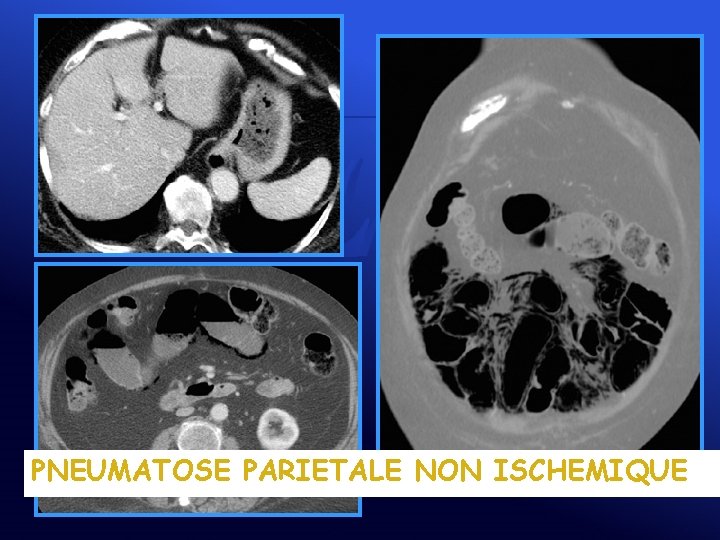

PNEUMATOSE PARIETALE NON ISCHEMIQUE

Après traitement par Flagyl® 3 mois plus tard

Pneumatose • ISCHEMIQUES • PNEUMATOSE KYSTIQUE INTESTINALE • Ischémie • Primitive (15%, colon) mésentérique • Secondaire (85%, grêle) – Gastrointestinale – Pulmonaire – Immunologique – Médicamenteuse (chimiothérapie, corticoïdes…)